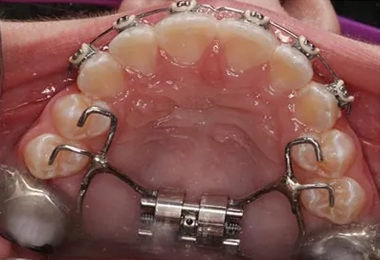

Orthodontic appliances are made to move teeth into better positions for health, proper function, and a beautiful smile. They may be removable or they may be brackets bonded to the teeth. By placing a constant, gentle force in a carefully controlled direction, braces slowly move teeth to the proper position.

Gone are the days when a metal band with a bracket was placed around each tooth. Orthodontic patients can have brackets that are bonded directly to the teeth. Wires are far less noticeable, and the latest materials are designed to move teeth faster with more comfort.

Our orthodontic services for straight teeth and optimal oral function may require treatment to guide the eruption of teeth. At The Kids Place, guidance of eruption is used to align teeth as they emerge from the gums. Encouraging the adult teeth to align naturally eliminates the need for mechanical movement of the teeth with braces and other oral appliances.

Pre-eruption guidance provides more stability for teeth. When teeth are guided into place naturally, the adult collagenous fibers provide stronger support for the teeth.

Different dental appliances are used to provide better spacing of the primary anterior teeth or to expand the arches to allow more space for teeth to come through the gums in the correct position. The appliance is typically worn at night so as not to interrupt regular daily activities, leading the permanent incisors into the correct positions to allow proper lateral spacing of the primary anterior teeth.

Once the incisors' positions are correct, the remaining adult teeth can come through with adequate space.

Gently guiding your child's dental arches back to normal dimensions will allow room for the permanent teeth to come in uncrowded, assist in correct muscle and tongue function, and even improve nasal breathing.